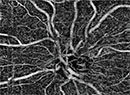

Will OCT Angiography Replace FA?

A close look at how this emerging imaging modality compares with the gold standard.